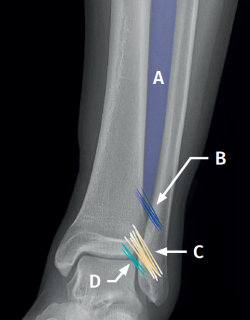

Sindesmosis (Figura 1)

Figura 1. Esquema de la sindesmosis anterior. A: membrana interósea; B: ligamento interóseo; C: ligamento tibioperoneo anterior; D: fascículo distal del ligamento tibioperoneo anterior.